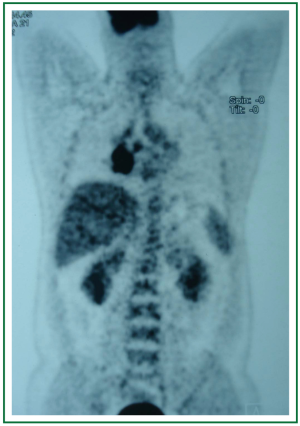

In physical examination, vital signs were normal, general and respiratory examination was unremarkable. Apart from a high fasting glucose level 177 mg/dL, eritrocyte sedimentation rate 48 mm/hr, liver function tests (AST: 73 IU/L, ALT: 92 IU/L), rutine laboratory analysis were normal. Respiratory function tests and oxygenation in room air were normal. The chest radiograph revealed prominence of right hilum and infiltration in the anterior segment of right upper lobe. A computed tomography scan revealed a 4 cm mass lesion in the right hilum and multiple mediastinal conglomerated lymph nodes (Figure 1). A PET/CT scan (Figure 2) demonstrated significantly increased activity (SUVmax: 9.74) at the right hilar mass lesion and right lower paratracheal (SUVmax: 3.57), subcarinal (SUVmax: 4.83), prevascular (SUVmax: 5.76) lymph nodes. Fiberoptic bronchoscopy showed mucosal distortion of right upper lobe. Pathologic examination of the mucosal biopsy revealed inflammation. Endobronchial ultrasound guided transbronchial needle biopsy from the hilar mass, right lower paratracheal and subcarinal lymph nodes revealed CD-45 positive normal lymphoid cells without any evidence of malignancy (Figure 3). Cervical mediastinoscopic biopsies of right lower paratracheal and subcarinal lymph nodes were undiagnostic. Diagnostic thoracotomy confirmed the diagnosis fibrosing mediastinitis. Hilar mass was a conglomerated lymph node showing dense hyalinized fibrous tissue with chronic inflammation (Figure 4). We administered 6 months of systemic corticosteroid and antituberculous therapy (Isoniazid, rifampicin, pirazinamid, ethambutol for two months and isoniazid, rifampicin for four months). A thorax tomography performed after discontinuation of therapy revealed similar findings with the postoperative thorax tomography.